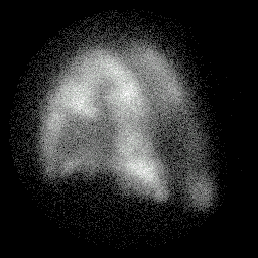

Example of COAD

Posterior Perfusion Posterior Ventilation

match_perf1.gif (19089 bytes) match_vent1.gif (20226 bytes)